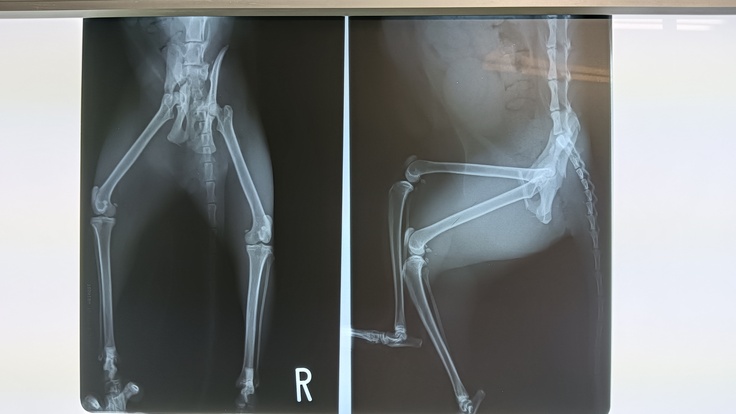

山口県で骨盤骨折をした三毛の野良猫を保護しました(おそらく車に轢かれたのだろうとレントゲン画像を見ながら説明を受けました)

10/7:保護日。歩き方もおかしかったので捕獲後すぐに病院に連れていきました。

レントゲンを撮ってもらったところ、骨盤骨折と診断されました。

その病院では整形をやめてしまったそうなので別病院を紹介していただきました。

血液検査、再度レントゲンを撮りました